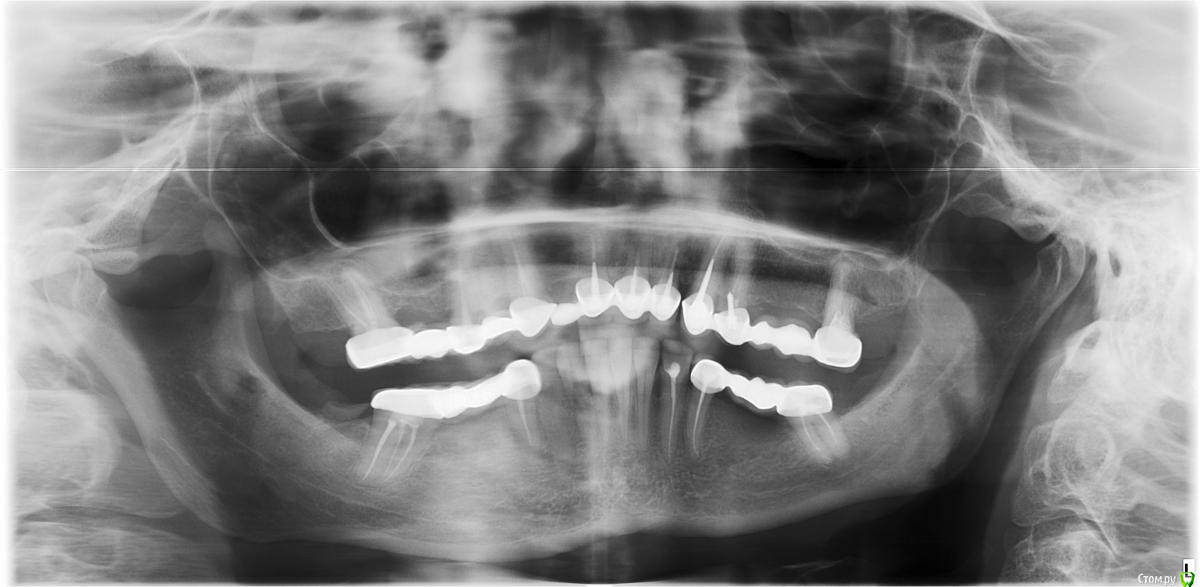

Arsinoya Опубликовано 5 октября, 2019 Автор Поделиться Опубликовано 5 октября, 2019 Прилагаю снимок Ссылка на комментарий

Arsinoya Опубликовано 5 октября, 2019 Автор Поделиться Опубликовано 5 октября, 2019 Здравствуйте, есть еще вот такой снимок, это как раз когда все боли начались, еще до перепломбировки каналов Ссылка на комментарий

Мартовский Опубликовано 7 октября, 2019 Поделиться Опубликовано 7 октября, 2019 Шестых зубов у вас нет, ни с лева ни с права, ни с верху ни с низу. Перфорация есть в левой четверке. Что делать, вам уже сказали: обратиться к другому врачу, по интернету такое не вылечить. Ссылка на комментарий